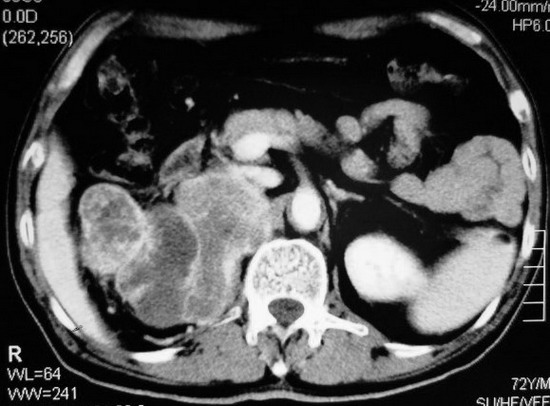

以下是引用杀毒软件在2008-11-17 19:15:00的发言:[br]考虑------右肾癌合并肾静脉---同侧肾上腺受侵可能性大

以下是引用zjzjr在2008-11-17 20:45:00的发言:[br]考虑------右肾癌合并肾静脉---同侧肾上腺受侵可能性大及腹膜后淋巴结转移.